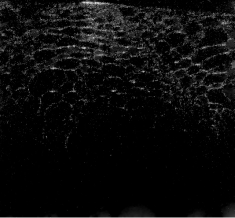

| interpolated ISAM | MBIR TV | MBIR DT-CWT | |

|---|---|---|---|

|

random |

![]() |

equispaced |

partial |

The cucumber tissues results in Figure 3 follow a similar trend to the beaded phantom, with very good preservation of structure for random and equispaced sub-sampling for both MBIR techniques. Again, partial measurements are significantly worse, with most of the structure degraded in the interpolated ISAM image.